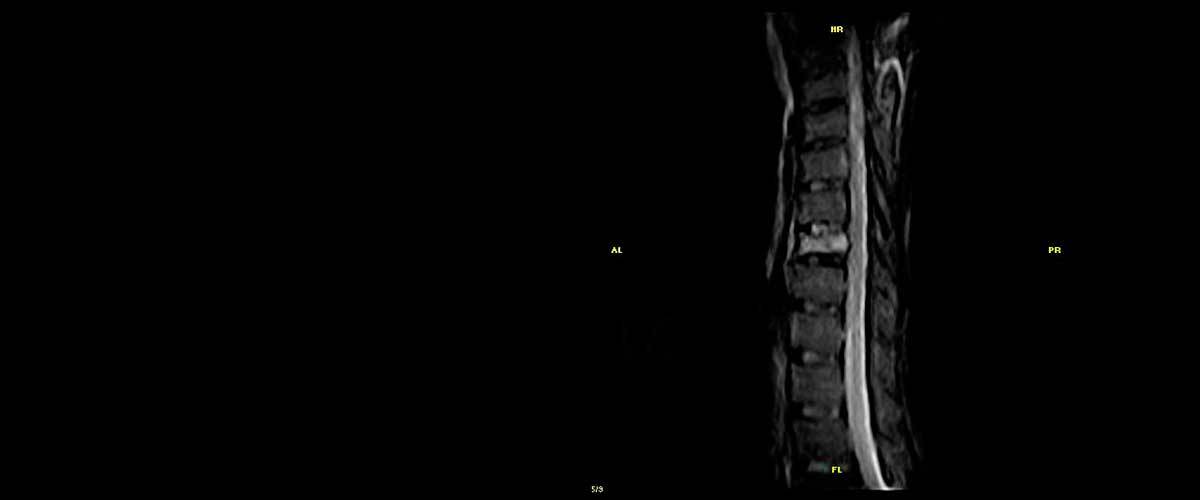

Contamos con equipos de resonancia magnética musculo-esquelética capaces de realizar exámenes con descarga de peso o bipedestación.

En nuestros centros se realizan estudios y diagnósticos de resonancia magnética musculo-esquelética

de Resonancia ,Magnética Musculo-Esquelética, de la marca italiana Esaote, es único en su diseño ya que nos permite realizar exámenes en bipedestación (el paciente estará de pie, para que se tenga otra perspectiva del comportamiento del cuerpo durante el examen).